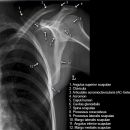

Schulter a.p. (Schultergelenk nach Grashey)

Beurteilungskriterien

- Außenrotation ->Tuberculum majus lateral randbildend, Innenrotation ->Tuberculum minus medial randbildend

- Gelenkspaltweite 4-6 mm

- Weite des subacromialen Raumes exakt nur in der 10 – 15° nach kaudal angulierten Aufnahme bestimmbar ("Morrison, Outlet View")! Normalerweise 1 - 1,5 cm, < 6 mm -> wohl pathologisch, Impingment röntgenlog. wahrscheinlich, Cave. rein klinische Diagnose!

- Normvarianten: Os glenoidale (akzessorischer Ossikel kaudal des Glenoids), persistierende Akromion- oder Korakoidapophyse, entwicklungsbedingte Pfannenranddefekte